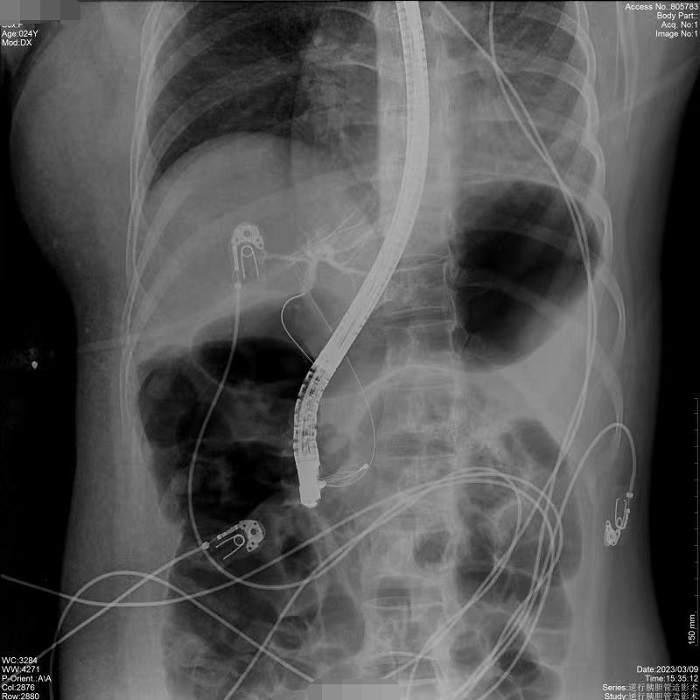

病例1:患者間斷上腹部脹痛4月,經(jīng)磁共振膽道水成像(MRCP)明確為膽總管結(jié)石、膽囊結(jié)石。常規(guī)手術(shù)需要膽總管切開(kāi)取石,考慮其自身的訴求,醫(yī)生決定嘗試為患者做內(nèi)鏡逆行膽管造影術(shù),幫助實(shí)現(xiàn)最小創(chuàng)傷及快速康復(fù)。術(shù)中,通過(guò)十二指腸鏡,將導(dǎo)絲通過(guò)十二指腸乳頭(即膽總管的下端開(kāi)口處)置入膽管內(nèi),在X線(xiàn)透視下注射造影劑造影,完成對(duì)膽總管內(nèi)情況診斷,并在診斷基礎(chǔ)之上完成取石治療。